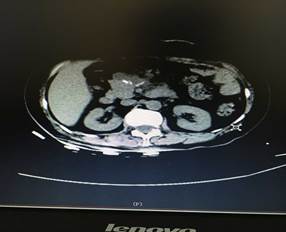

充分術(shù)前準備后,在肝膽外科團隊努力及麻醉科的鼎力支持下,歷經(jīng)4個多小時,大家成功在腹腔鏡下為患者進行了胰腺巨大腫瘤及胰腺體尾端切除,脾臟、膽囊切除手術(shù)。術(shù)后第四天患者便進食流汁,下床活動,復(fù)查情況良好(圖2、圖3),患者和家屬臉上都露出了久違的笑容。

圖2

圖3